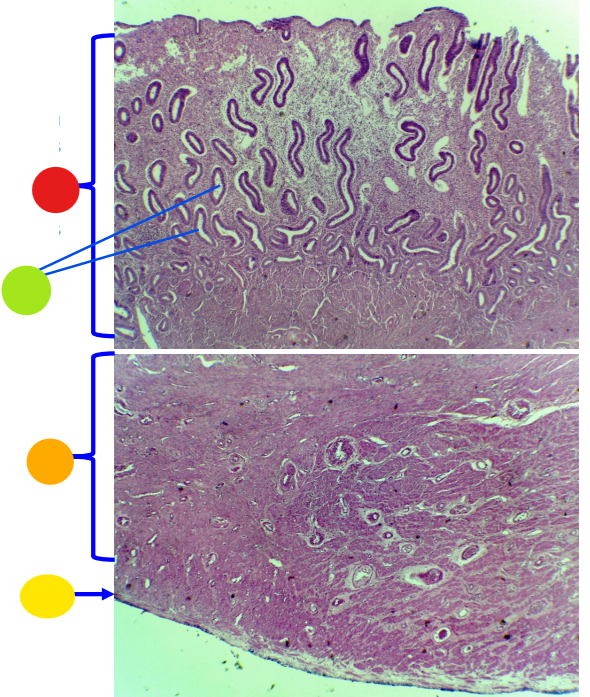

red

granulosa cells

orange

primary oocyte

what is this

primary follicle

red

granulosa cells

orange

thecal cells

yellow

zona pellucida

What is this

secondary follicle

red

papillae

orange

stratum corneum

yellow

non-keratinized stratified squamous epithelium

light green

lamina propria

What is this?

vagina

red

non-keratinized stratified squamous epithelium

orange

stratum corneum (missing)

yellow

lamina propria

light green

smooth muscle

What is this?

vagina